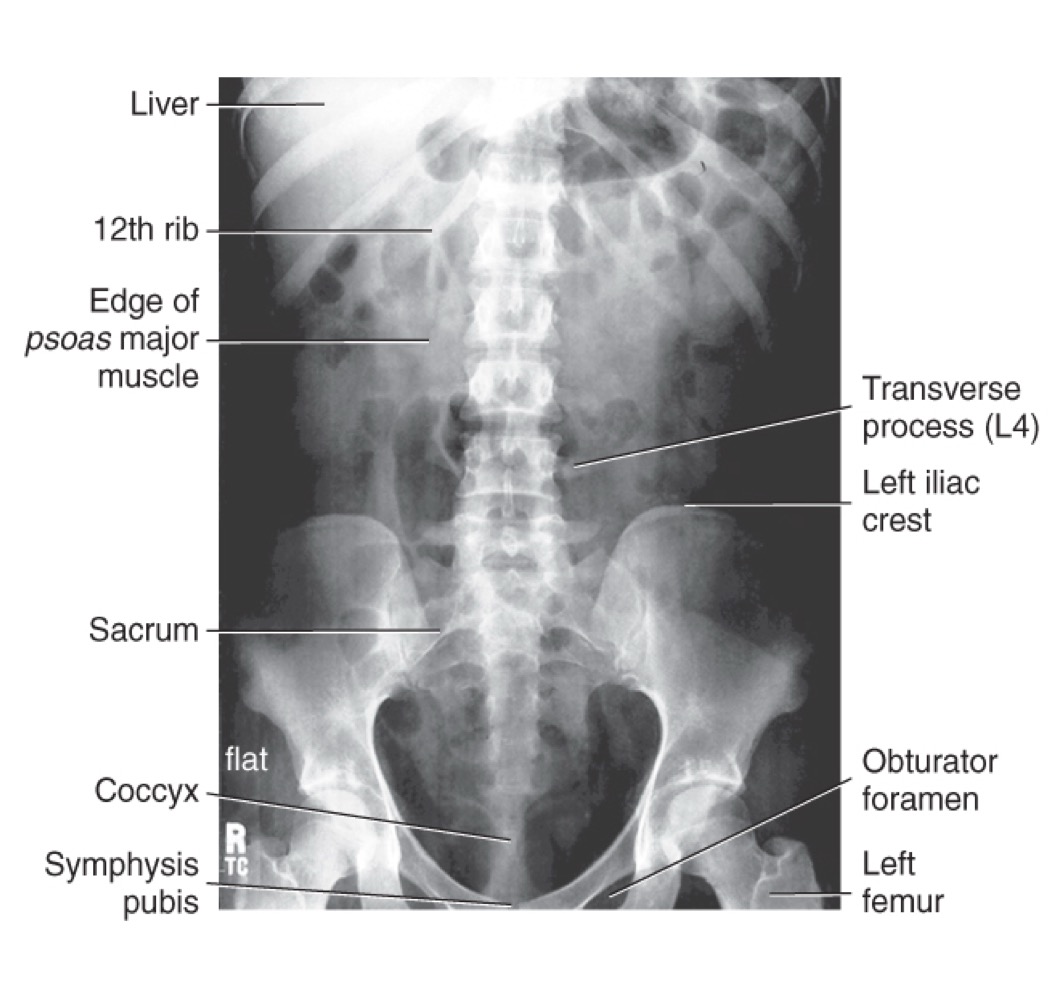

KUB (Kidney-Ureter-Bladder)

A radiographic view of the abdomen used to evaluate abdominal and urinary structures; may not show all structures, but helps visualize soft tissues and can indicate exposure quality (e.g., borders of psoas major muscles).

Psoas major

A large muscle of the posterior abdominal wall; its borders are visible on a properly exposed KUB and serve as a radiographic exposure indicator.

Liver

Iliac crest

The superior border of the pelvis; a landmark used to estimate imaging levels (e.g., around L4–L5).

Symphysis pubis

The cartilaginous joint at the front of the pelvis where the two pubic bones meet.

AP supine abdomen (KUB)

Anteroposterior view of the abdomen with the patient lying on their back; used in routine abdominal imaging.